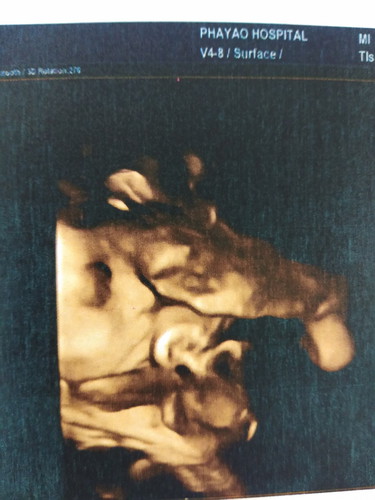

วันนี้ไปซาวน์มาคุณหมอบอกน้องนน.น้อยไปหน่อยค่ะ 1700 กรัม อายุครรถ์ 31 สัปดาห์ ขอคำแนะนำอาหารที่ทานแล้วทำให้น้องนน.เพิ่มหน่อยค่ะ